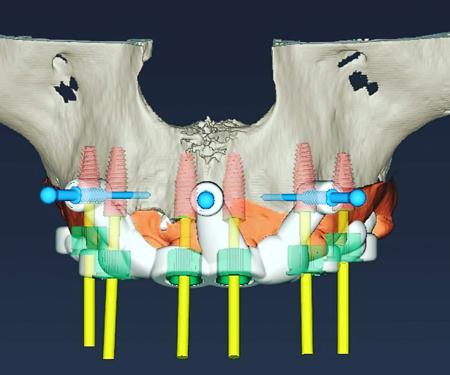

种植修复

打印-种植钴铬瓷牙

打印-种植桥